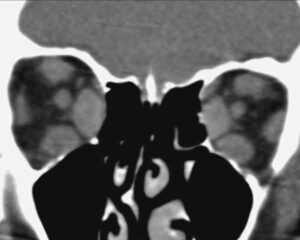

Orbitopatie tiroidee: aumentano i casi

Un italiano ogni 10 soffre di problemi alla tiroide, con un'incidenza piu' elevata tra le quarantenni. (altro…)